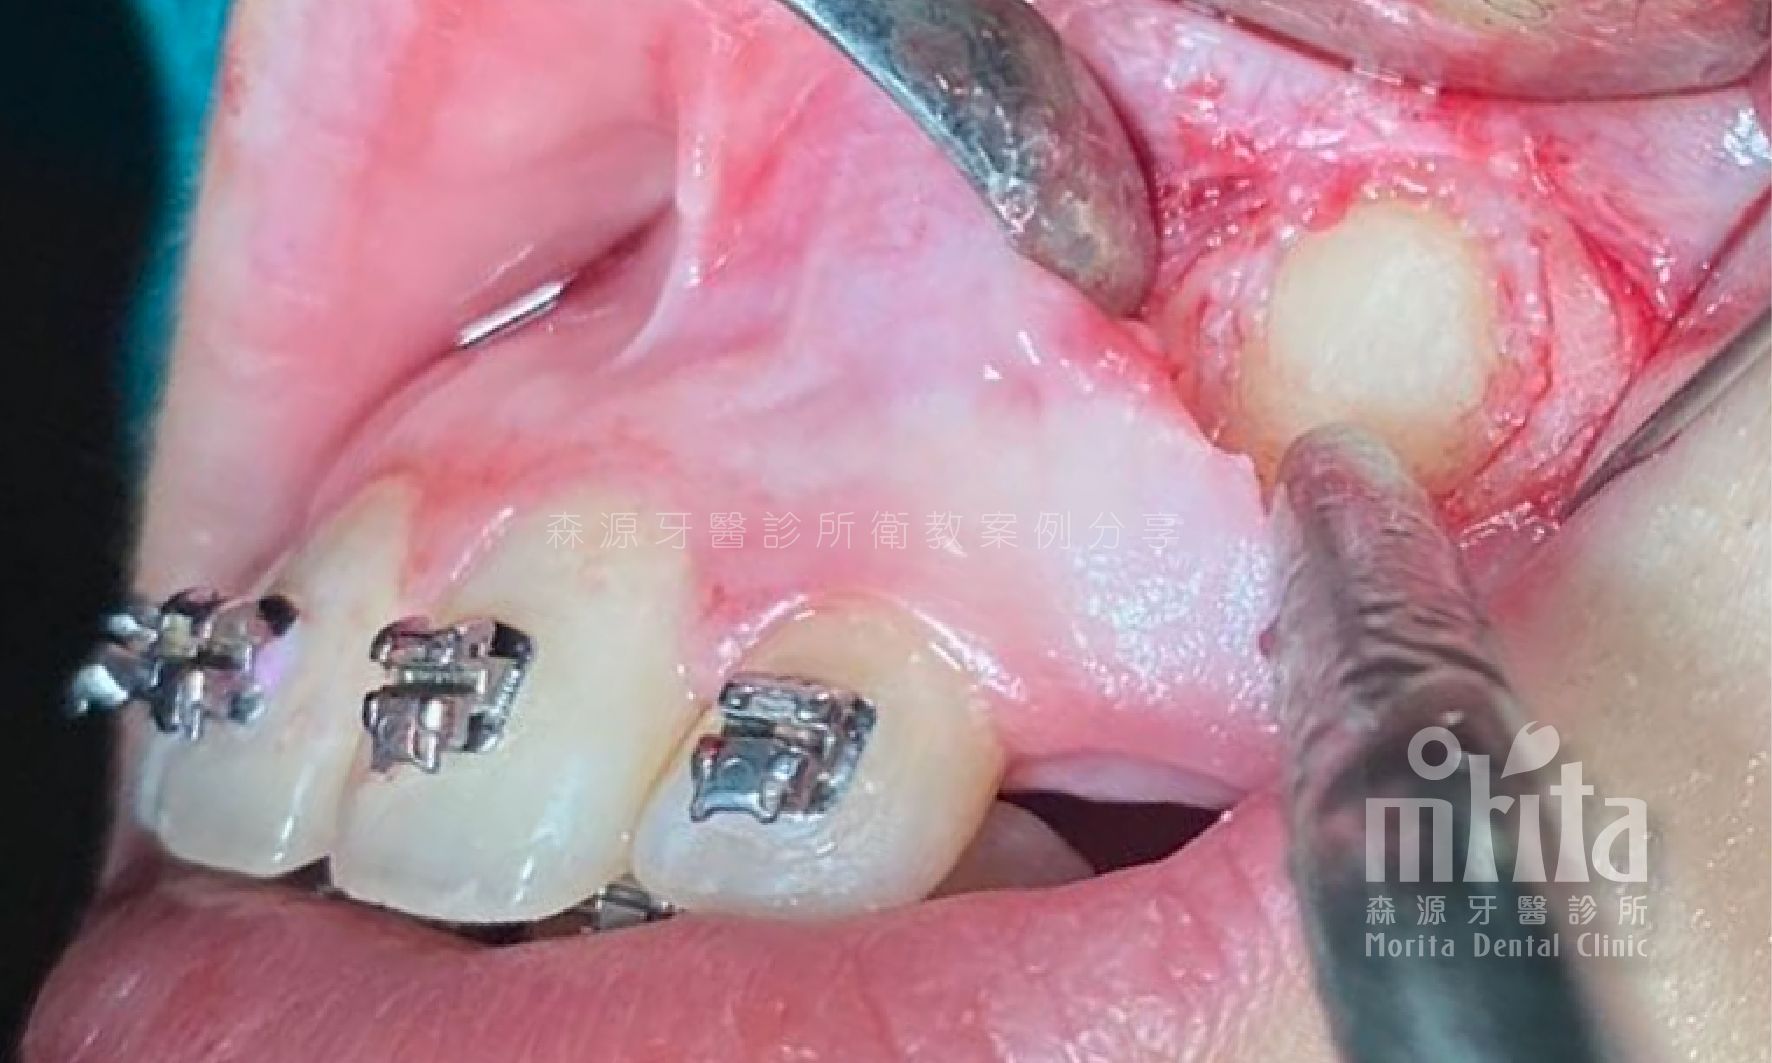

可能因為過早地缺牙,可能因為齒列過於擁擠,又或是老天爺開的玩笑,造成有些該⻑出來的牙齒⻑不出來,需要在阻生齒還有生⻑潛力時拉一把,讓牙齒順利萌發。

阻生齒 Impaction